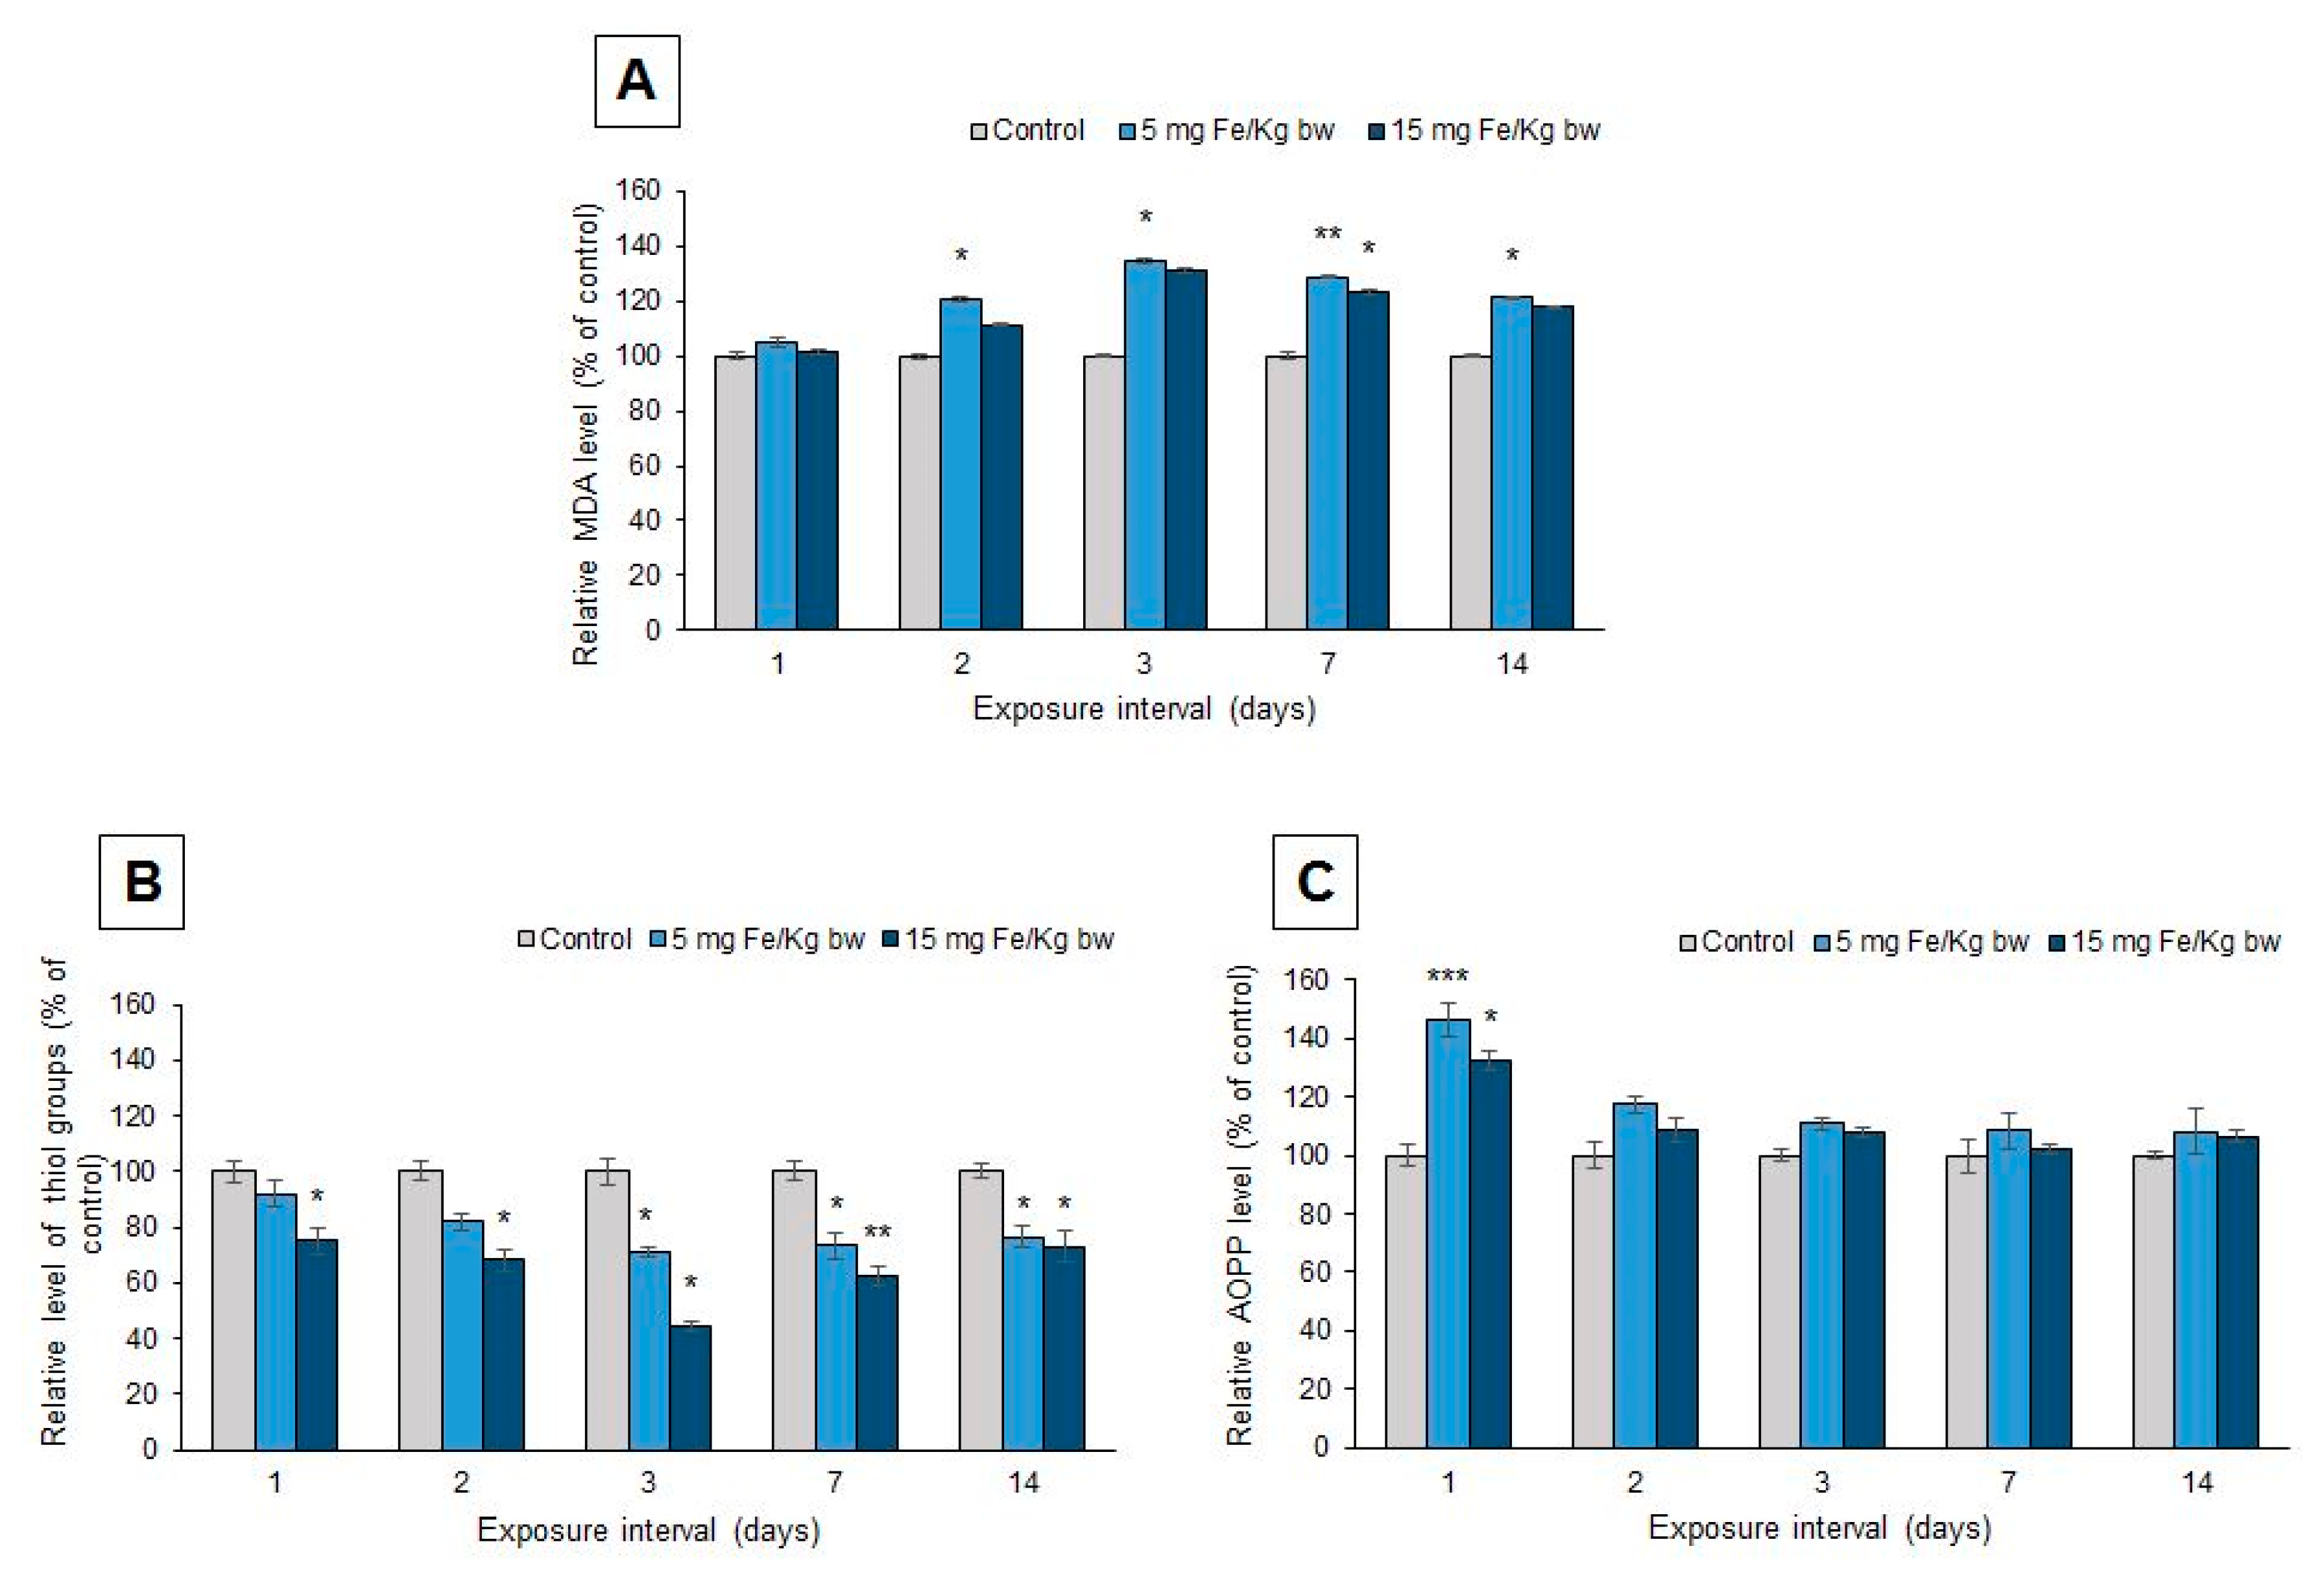

3.6. Oxidative Modifications